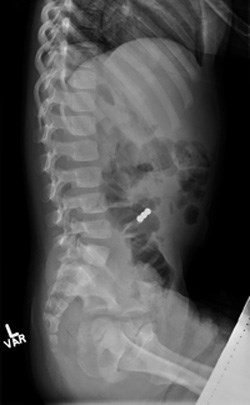

TORONTO – Desk magnet sets, consisting of over a hundred small spherical magnets, were all the rage about six years ago. Though marketed as ‘adult desk toys’, they made their way into the hands of children across the country and proved to be a danger to curious children who ingested them. These tiny magnets are 10 times more powerful than standard fridge magnets and could attract each other through loops of the gastrointestinal tract, could damage or puncture the bowel or stomach wall, and could potentially lead to death.

The researchers examined patient records for magnet-related injuries and compared data from two years before the mandatory recall (2011 and 2012) with data from two years after the recall (2014 and 2015). They found that there was a significant decrease in multiple mini-magnet ingestion following the mandatory product recall. From 2011 to 2012, there were 22 cases of multiple magnet ingestions leading to six operations and nine endoscopic procedures. In contrast, in the two years after the ban (2014 and 2015), there were only five cases of multiple magnet ingestion; one child required an operation and four required endoscopy.